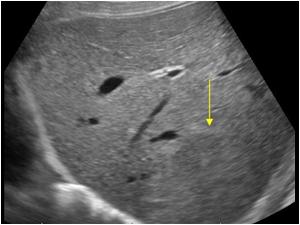

Polycystic liver disease

Multiple cysts with posterior acoustic enhancement, consistent with polycystic liver disease.

What is this pathology?